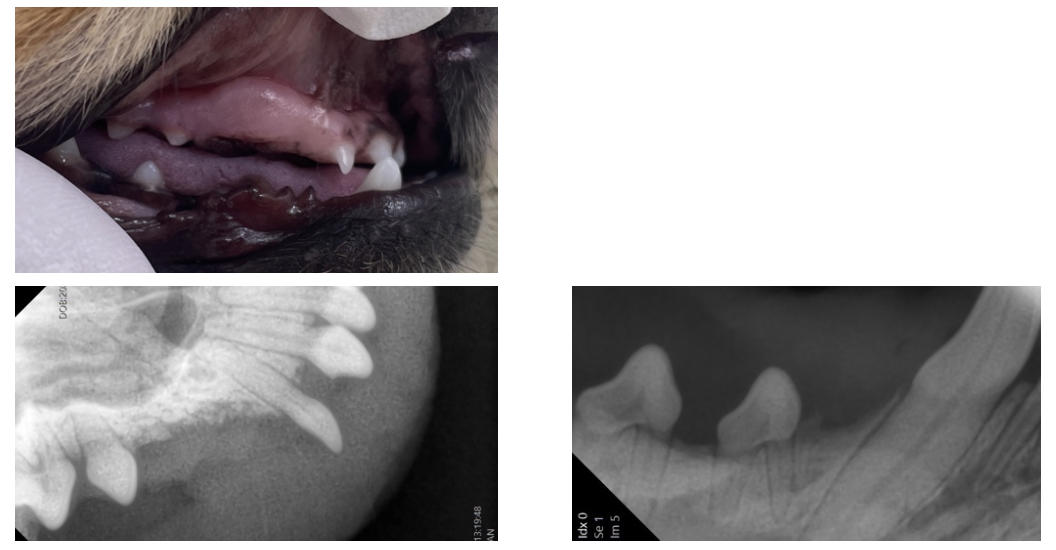

本来犬の永久歯は計42本ですが、この症例では計6本の歯が目視では確認できません。

歯科レントゲン検査で歯肉の下に隠れている歯(埋伏歯・まいふくし)の有無を確認する必要があります。

右上顎犬歯(赤丸)と右下顎第一前臼歯(黄色丸)が埋伏歯であること、その他の歯は生まれつきないことがわかりました。

埋伏歯をそのままにしておくと将来的に『含歯性嚢胞』といった病気になる可能性があるため、ご相談の上、麻酔をかけて抜歯することになりました。